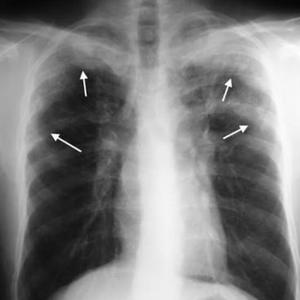

Löffler's syndrome or Loeffler's syndrome is a disease in which eosinophils accumulate in the lung in response to a parasitic infection. ... If the cause is unknown, it is specified and called "simple pulmonary eosinophilia". Cardiac damage caused by the damaging effects of eosinophil granule proteins.